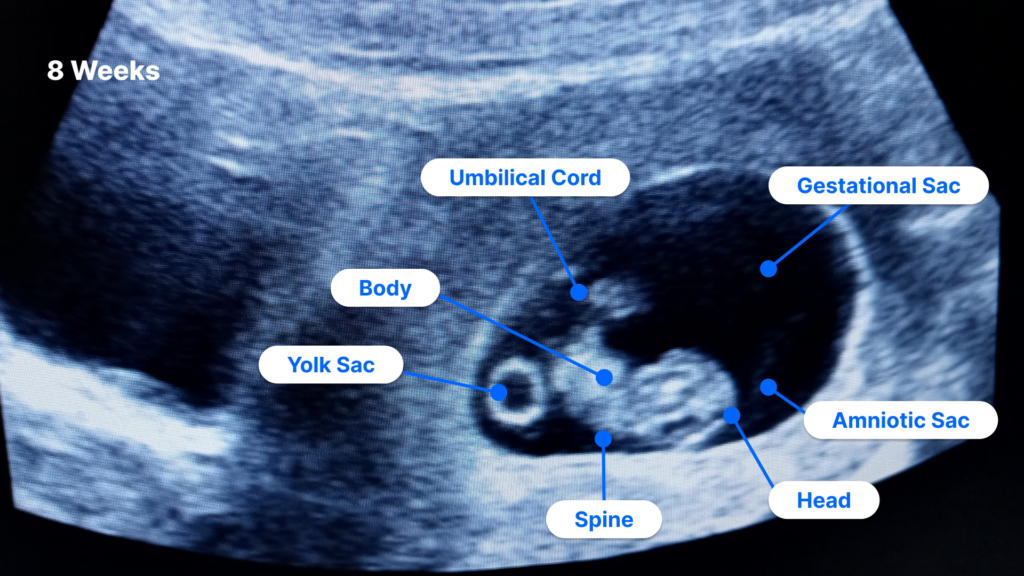

Ultrasound Pictures 8 Weeks Pregnant Vrogue co

How Does A Miscarriage Look Vrogue co